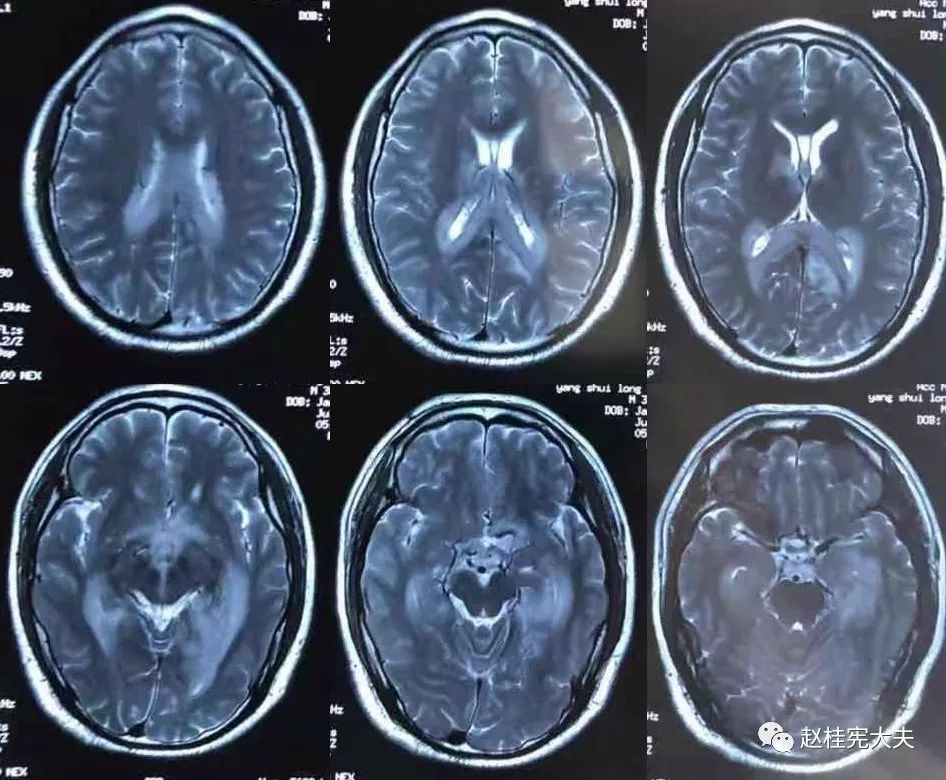

2018.7.6头颅MRI:胼胝体、穹隆及双侧脑室旁、基底节区、右侧延髓、桥臂异常信号,脱髓鞘病变考虑。头颅MRS:左枕叶病变区MRS显示:NAA下降,Cho升高,Cho/NAA=3.86,并见倒置乳酸峰。

2018.7.10磁共振增强:脑室周边病灶轻度强化。

7.20复查头颅MRI平扫:胼胝体、穹隆及双侧脑室旁、基底节区、右侧延髓、桥臂广泛信号异常,对照前片(7.10)范围明显缩小。

2018.10复查头颅MRI:胼胝体压部、左侧部分枕颞叶、侧脑室枕角旁、中脑脱髓鞘病变,视神经脊髓炎谱系病?结合对照前片(7.4)病变范围有所缩小。

我看到患者时的思考:当了解了患者前期诊疗经过后,在看到患者磁共振片子时,我的第一反应就是淋巴瘤。尽管患者激素治疗后症状有好转,病灶在磁共振上看起来也是有好转,但淋巴瘤也会出现这样的表现。

我对满脑室边的病灶的体会是:遇到这样的病例,首先要考虑感染、肿瘤(如室管膜瘤、生殖细胞瘤、淋巴瘤或转移瘤脑室播散等等),炎症要放到后面去考虑,脱髓鞘的诊断要打个大大大大的?。炎症中,血管炎不像,自免脑也不是很支持,尽管边缘系统似乎也有受累,但患者边缘叶脑炎的精神、行为异常、癫痫等症状很少,而且磁共振上看去除了边缘系统,整个脑室系统都有受累,这个和常见自免脑不符。视神经脊髓炎谱系病?尽管病灶在水通道蛋白富集区,但这样的视神经脊髓炎(视神经和脊髓均未受累,近脑室边的异常信号)至少罕见,即使诊断,也应该是排除其它的疾病后才可能考虑。

患者住院期间还请眼科会诊,除双眼玻璃体轻度浑浊,视力、视野、OCT均未见明显异常,未建议行玻切明确诊断。患者入院后嗜睡症状有加中,但一直未诉头痛,仅是头昏,静滴甘露醇症状减轻不明显。复查头颅磁共振平扫+增强:病灶范围较前明显扩大。轻度强化。